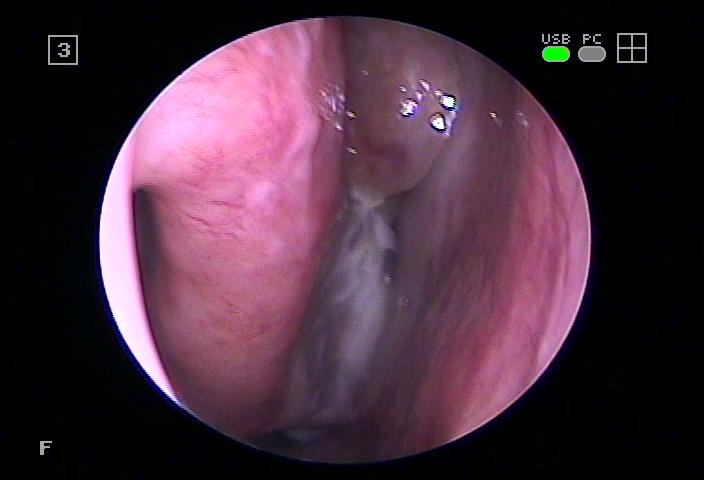

자연공 케어가 주요 포인트. 앞서 언급한 바와 같이 부비동은 얼굴에 4쌍 존재하는데, 이때 자연공의 영향으로 환기 및 노폐물의 배설이 이루어지고 섬모 기능 및 분비물의 양상 등에도 영향을 미친다고 했습니다.

특히 이곳이 막히면서 염증이 발병하고 산소를 공급하기 위해 뇌까지 전달되는 과정이 제대로 이뤄지지 않아 점차 심각해지는 양상을 보였습니다.

따라서 수원축농증이비인후과에서는 부종으로 인해 부어있는 점막을 관리하고 이를 완화하는 자극요법으로 비강 내에 쌓여있는 노폐물을 제거하여 자연스러운 자연공의 개방을 이끌어낼 수 있었습니다.

수원축농증이 이비인후과에서는 만성으로 이어지면 다른 곳까지 영향을 미치게 되어 문제를 일으킬 수 있다고 했습니다. 예를 들어 결막염 또는 중이염과 같은 증상으로 이행될 수 있기 때문에 본원에서는 3분간 실시하는 점막재생치료를 통해 이곳의 개선을 목표로 시행하고 있었습니다.

본원에서는 자신의 체질과 양상을 고려한 맞춤 한약을 통해 호흡기 정상화를 목표로 진행하고 있으며, 직접 개발한 카테터를 사용하여 구석구석 누적된 고름을 제거하고 점막치유를 시행하고 있었습니다.